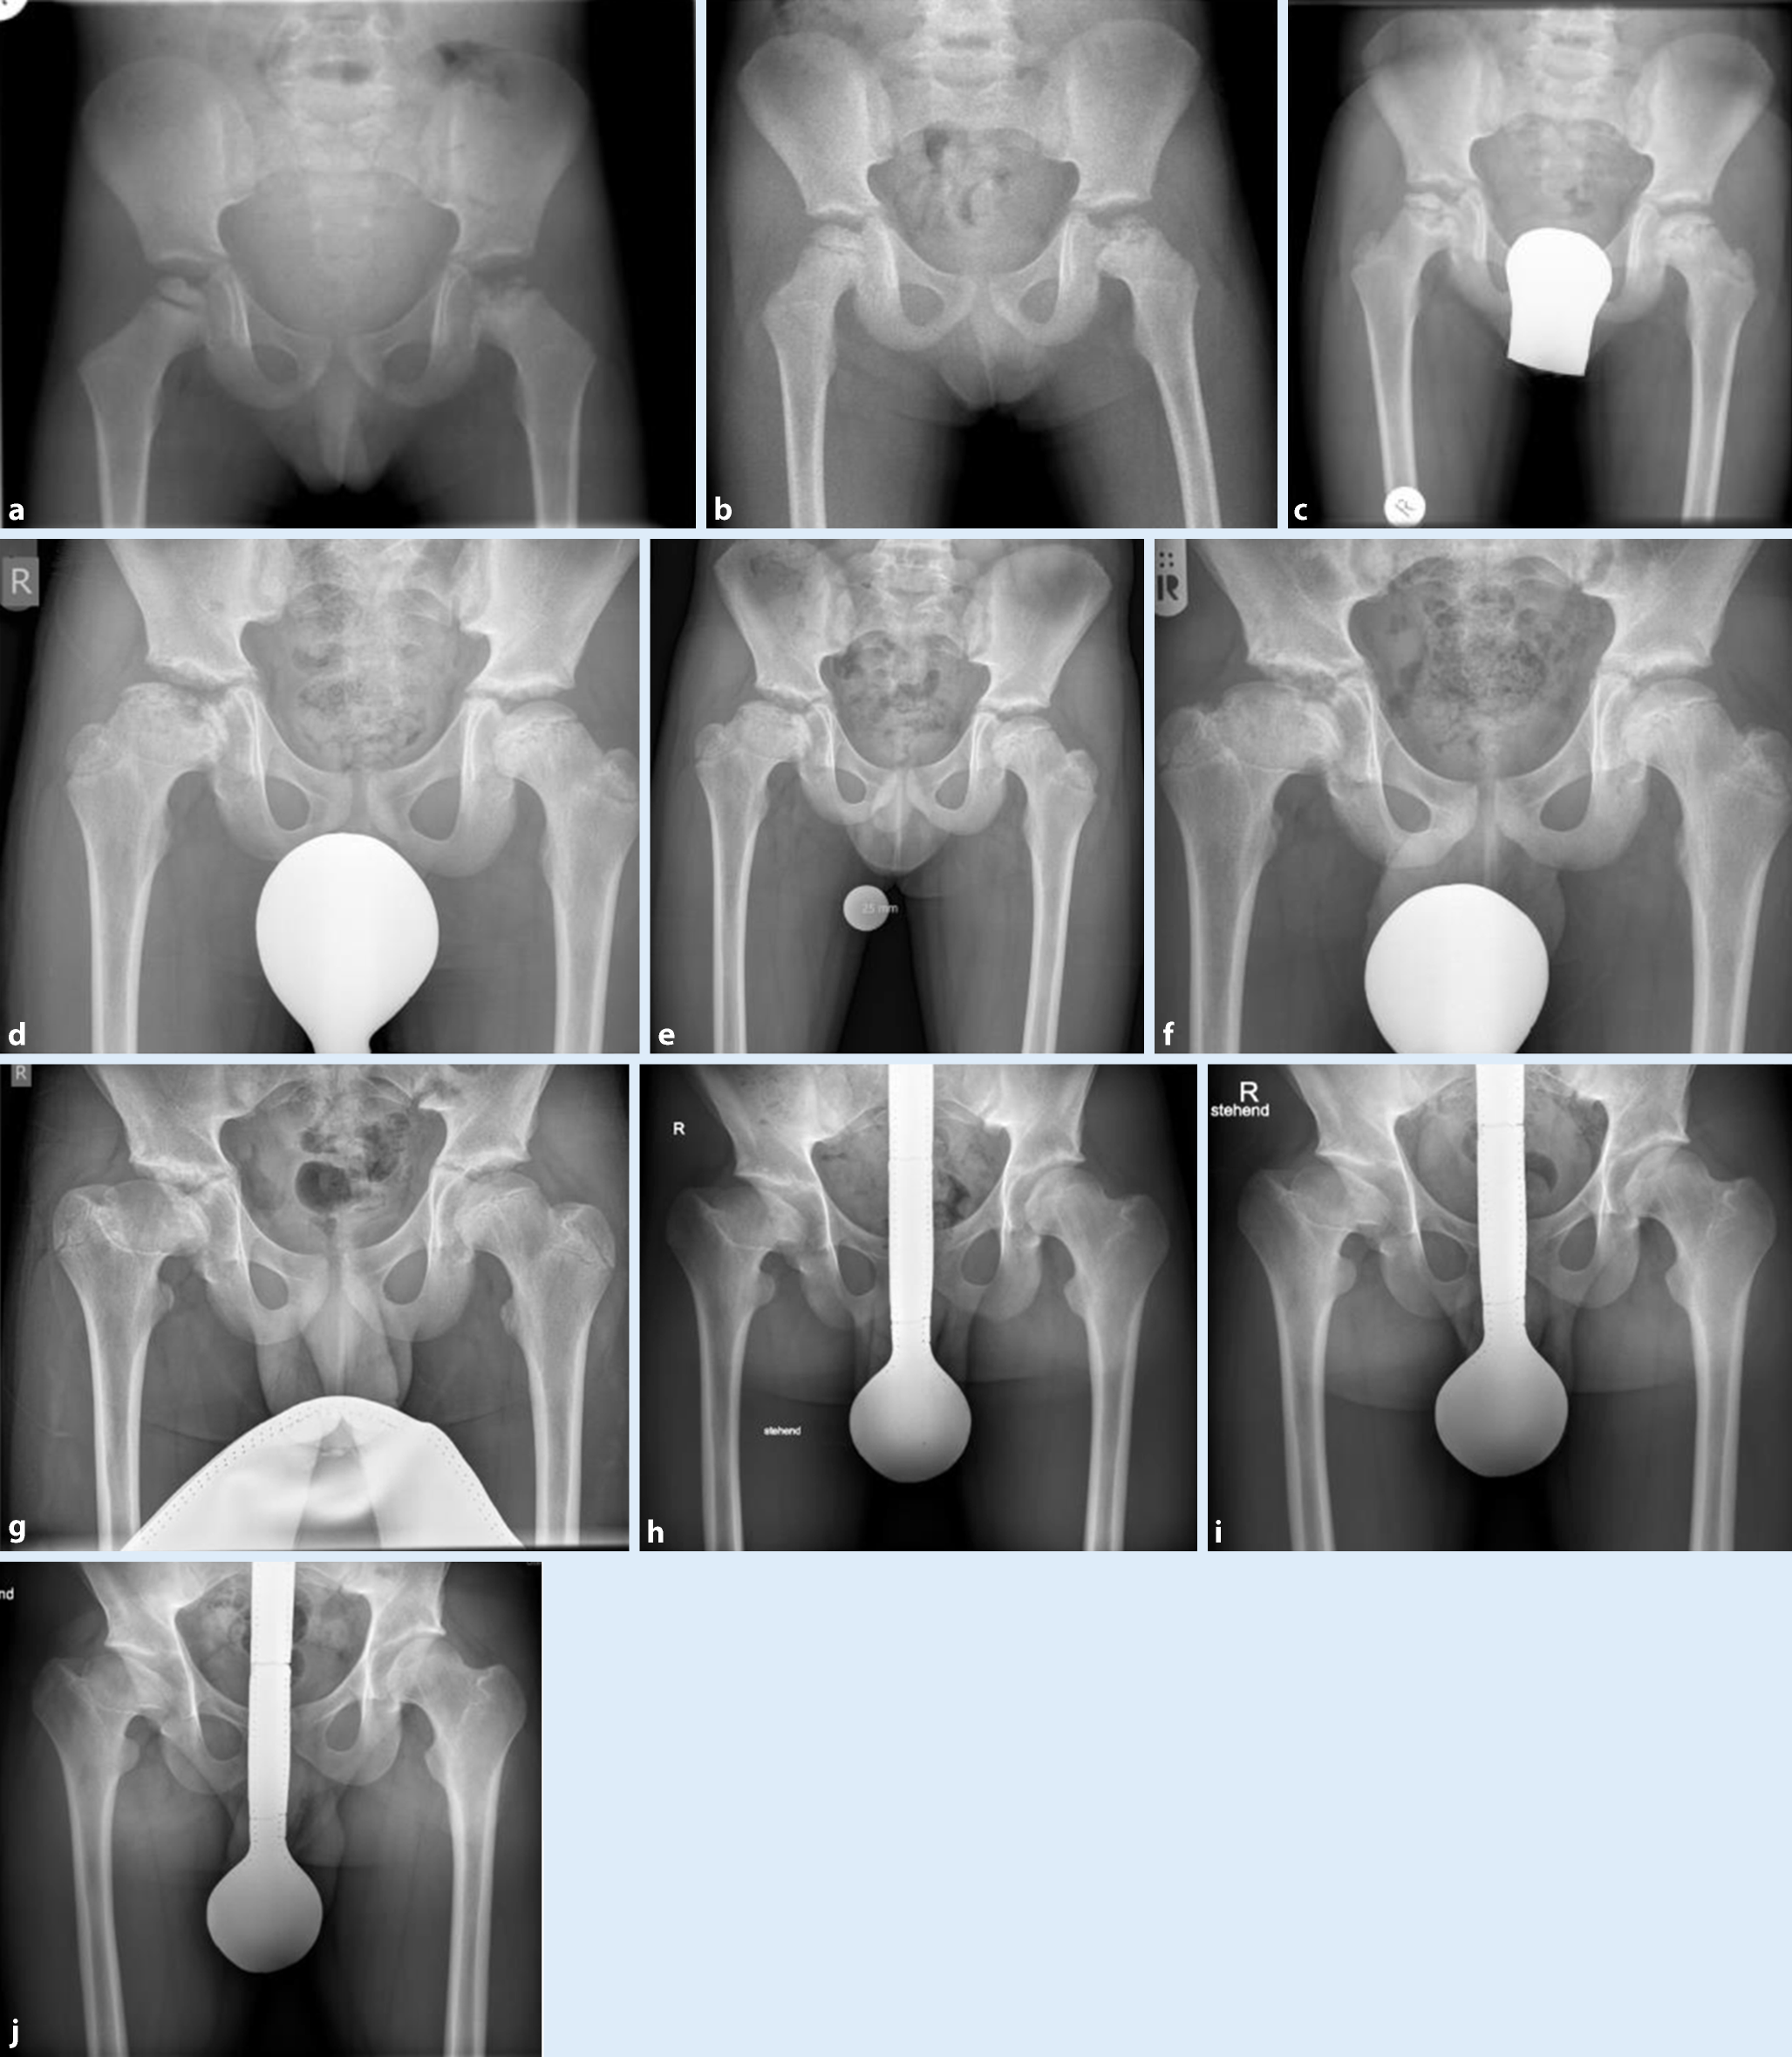

In etwa 10 % der Fälle tritt die Erkrankung zeitverzögert und unabhängig auch an der kontralateralen Hüfte auf ([1]; Abb. 1).

Abb. 1

Typischer Krankheitsverlauf bei Morbus Perthes. Beachte: unterschiedlicher Heilungsverlauf bei frühem und spätem Beginn der Erkrankung: linkes Hüftgelenk mit 3 Jahren und rechtes Hüftgelenk mit 7 Jahren. a 3 Jahre 4 Monate, b 4 Jahre 10 Monate, c 7 Jahre, d 9 Jahre 9 Monate, e 10 Jahre 8 Monate, f 12 Jahre, g 13 Jahre, h 15 Jahre, i 17 Jahre, j 19 Jahre

Der Verlauf wird röntgenmorphologisch in 4 Erkrankungsstadien [8] gegliedert, die sich über einige Jahre erstrecken (Abb. 1 und 2):